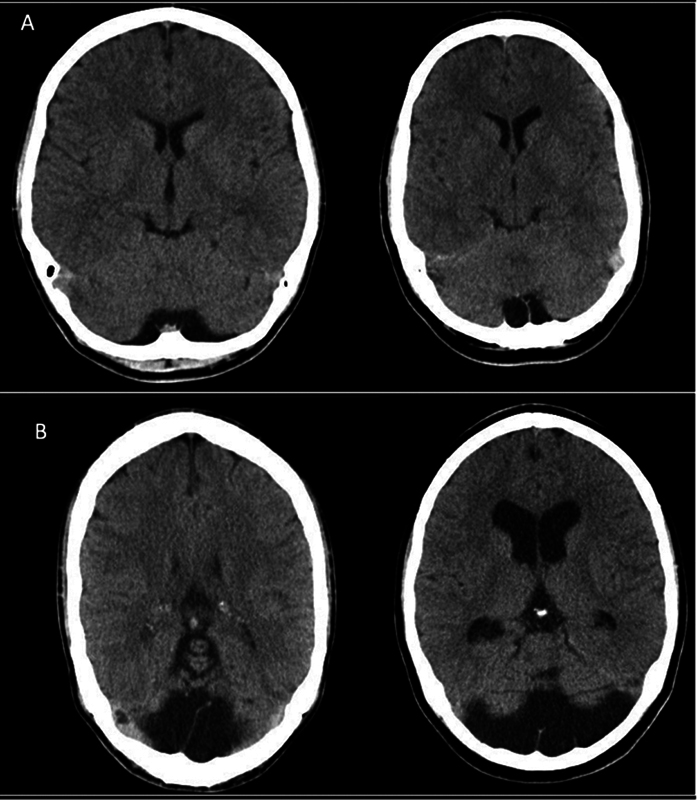

Background  The clinical significance and incidence of isolated mega cisterna magna (MCM) have been thoroughly investigated. While MCM has been reported in association with psychiatric disorders in adults, current study sought to report its incidence and relationship with gender and age in a consecutive series of patients without psychiatric comorbidities. Materials and Methods  We retrospectively reviewed 1,016 consecutive computed tomography scans of patients between the age of 1 and 80 with a history of minor head trauma, headache, or vertigo from April to August 2023. Two perpendicular diameters inside the MCM were measured: the first diameter (D 1 ) was measured longitudinally on the midsagittal plane (anteroposterior diameter), whereas the second one (D 2 ) was measured transeversely (transverse diameter). An MCM with D 1  > 20 mm was defined as "huge MCM." The relationship between age, gender, and the two diameters were subsequently analyzed. Results  Over a course of 5 months, 92 cases with MCM, including 76 men, were evaluated. The mean age of MCM cases was 35.31 ± 26.14, with no significant relationship observed between age and MCM. No significant difference in D 1 was found between genders, while D 2 significantly differed between men and women ( p  < 0.029). "Huge MCM" was exclusively observed in 18 men ( p  < 0.035). There was also no significant correlation between D 1 and D 2 . Conclusion  MCM appears to be a normal variation in the general population with no clinical significance. Despite the small sample size, the current study can provide a foundation for further studies to investigate the correlation of isolated MCM with different aspects of cognitive functions and its potential clinical relevance.